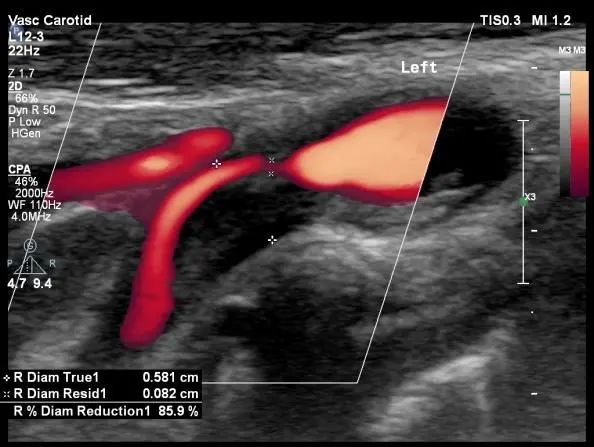

患者,男,52岁,发作性左侧肢体活动不灵就诊。头MRI提示未见异常病灶。TCD提示右侧大脑中动脉重度狭窄。通过血管超声的筛查,找到了临床事件的“始作俑者”-责任血管。

“健康”体检者。颈动脉超声提示颈动脉重度狭窄。TCD提示颅内侧支循环代偿充分。无创的头颈血管超声的一体化评估是筛查脑血管病高危人群的首选,是“前哨兵”。